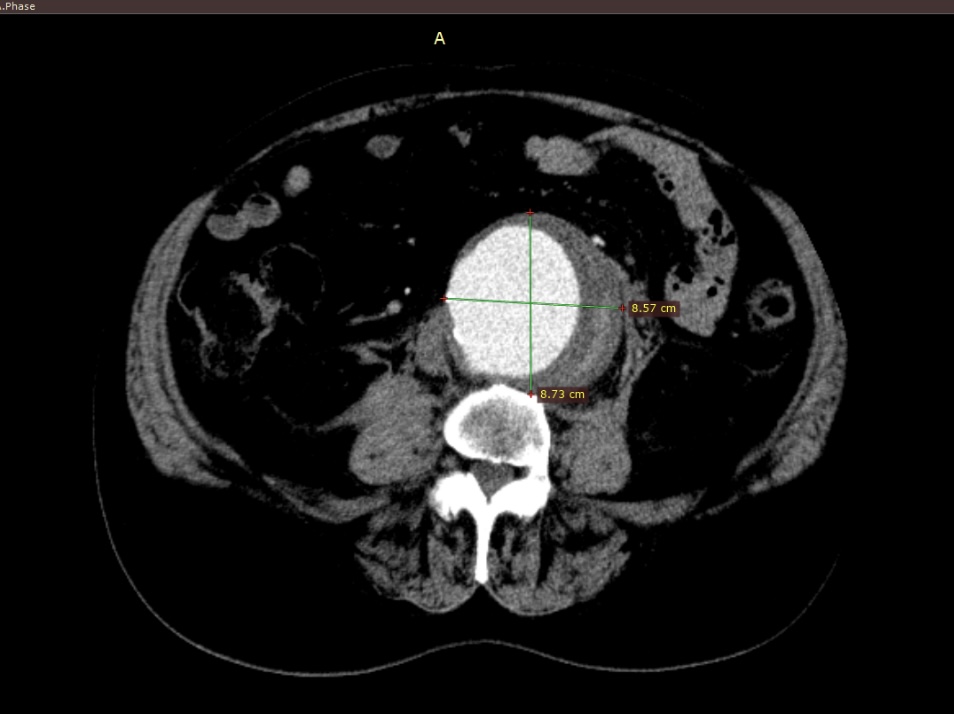

Під час повторного КТ там встановили, що аневризма досягла понад 10 см та супроводжувалася розривом задньої стінки, через що утворилася велика заочеревинна гематома, яка становила пряму загрозу життю. Команда судинних хірургів оперативно провела резекцію ураженої ділянки аорти та виконала лінійне алопротезування.